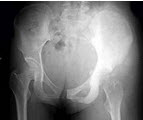

41、单项选择题

女,16岁,左臀部疼痛伴发热2个月,摄片如图所示,最可能的诊断是()

A.左髂骨成骨肉瘤

B.左髂骨急性化脓性骨髓炎

C.左髂骨软骨肉瘤

D.左髂骨网状细胞肉瘤

E.以上均不正确